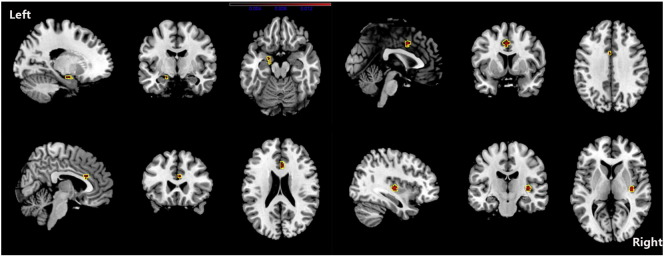

Although PAG increase was found in one study (Rocca et al., 2006), we found no overall increase in GM in patients with migraine. The ALE results showed that, compared with HC, migraine was associated with a common core set of decreases in GM volume in the bilateral inferior frontal gyri, the right precentral gyrus, the right cerebellar culmen, the left middle frontal gyrus and the left cingulate gyrus (see Fig. 2 and Table 5). Changes in the volume of GM in the right claustrum, left cingulated gyrus, right anterior cingulate, amygdala, and left parahippocampal gyrus were negatively related to the estimated frequency of attack (see Fig. 3 and Table 6).

Fig. 3.

ALE map investigating regional difference of GMV related to estimated frequency of headache attack in Migraine patients. Red colour show grey matter decreases, they include right claustrum, left cingulated gyrus, right anterior cingulate, amygdala and left parahippocampal gyrus. (ALE maps were computed at a threshold of p < 0.001, with a minimum cluster size of K > 100 mm3 and visualized using MRIcron). Talairach coordinates of clusters showed in this image are reported in Table 6.

Table 6.

Regional difference of GMV related to estimated frequency of headache attack in migraine patients.

| Clusterno. | Volume (mm3) | Weighted center (x, y, z) | x | y | z | ALE value (× 103) | Label | ||

|---|---|---|---|---|---|---|---|---|---|

| 1 | 496 | 36.8 | − 15.9 | 3.4 | 36 | − 16 | 4 | 15.792 | Right claustrum |

| 2 | 424 | − 1.4 | 6.7 | 39.4 | − 2 | 6 | 40 | 13.774 | Left cingulated gyrus B32 |

| 3 | 264 | 4.1 | 23.2 | 22.9 | 4 | 22 | 22 | 10.652 | Right anterior cingulate BA24 |

| 4 | 256 | − 18.7 | − 6.7 | − 17.3 | − 20 | − 4 | − 18 | 9.541 | Left parahippocampal gyrus amygdala |

| − 18 | − 10 | − 16 | 9.409 | Left parahippocampal gyrus BA34 | |||||